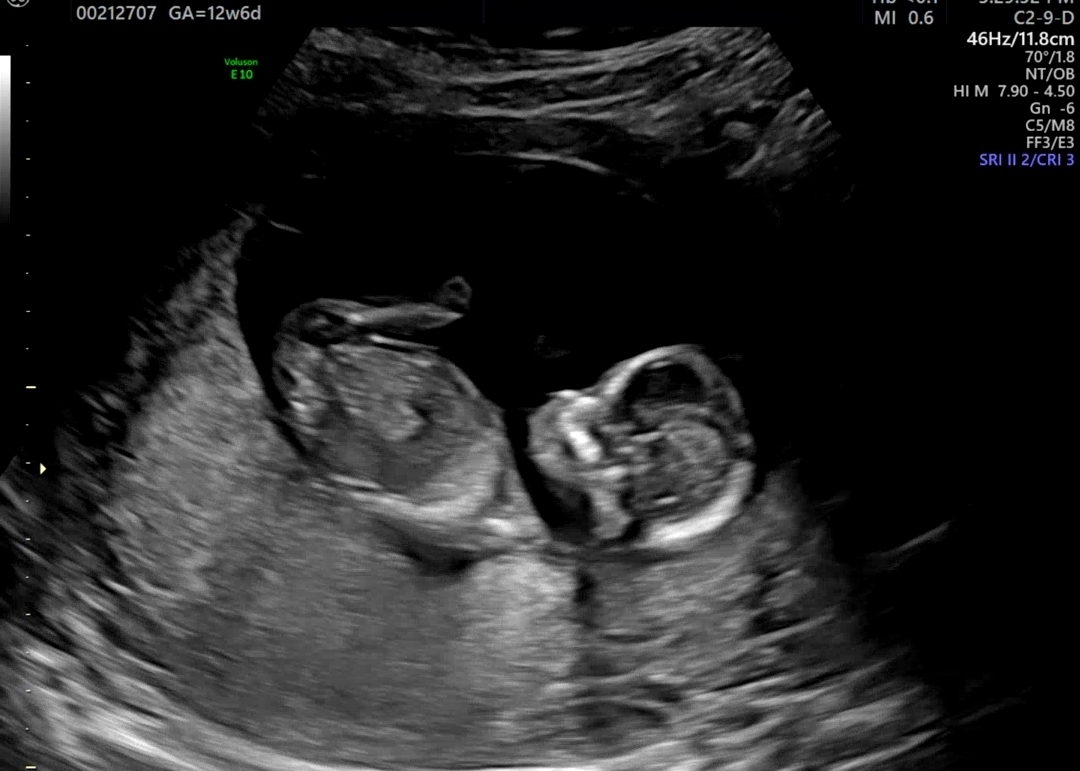

12주6일 성별 보이시나용??

딸도 아들도 너무 사랑스럽지만 궁금한건 못참게써용!ㅋㅋㅋㅋ 각도법..고수님들 계신가요? 재미로한번 봐주세용

생식기부위가 안보여요 ㅠ

허벅지에 가려 보이지않아요ㅎ